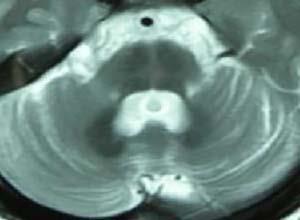

简介皮克病(Pick’s disease)是罕见的缓慢进展的认知与行为障碍性疾病,Pick(1892)首先描述了一组以额颞叶萎缩为病理特征的病人,表现为行为异常、失语和认知障碍等,他报道的第一例71岁男性,表现为进行性精神衰退和极严重失语,尸检发现左颞极皮质萎缩极严重;其后报道的4例特别强调病人有进行性语言障碍。